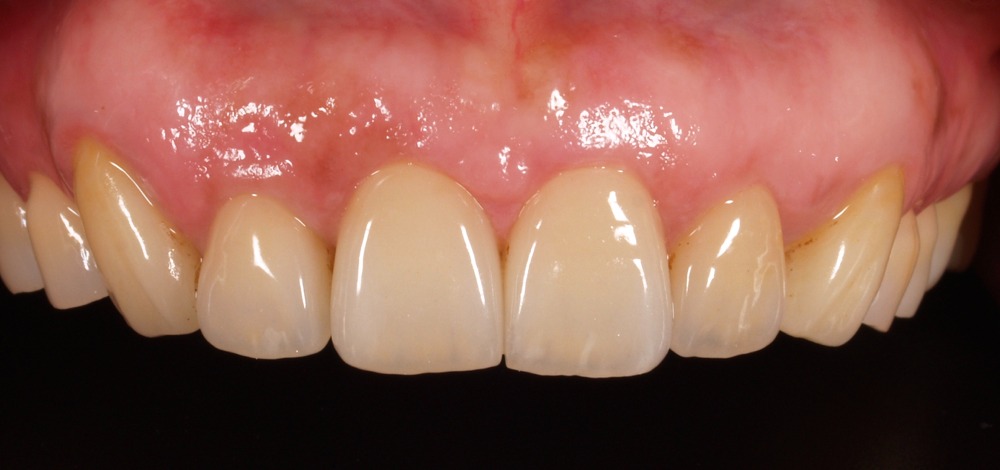

ファイナルレストレーション

前歯のインプラント治療では、見た目の良し悪しが患者様の満足度を大きく左右します。しかし、誰が見てもインプラントと分からないほどの自然な美しさを実現するのは、非常に困難です。

優れたインプラントクリニックは、歯科技工士を大切にします。歯科医師と技工士のチームワークが成り立って初めて高品質のインプラント治療が可能になります。目に見えている人工歯は技工士の作品なのです。